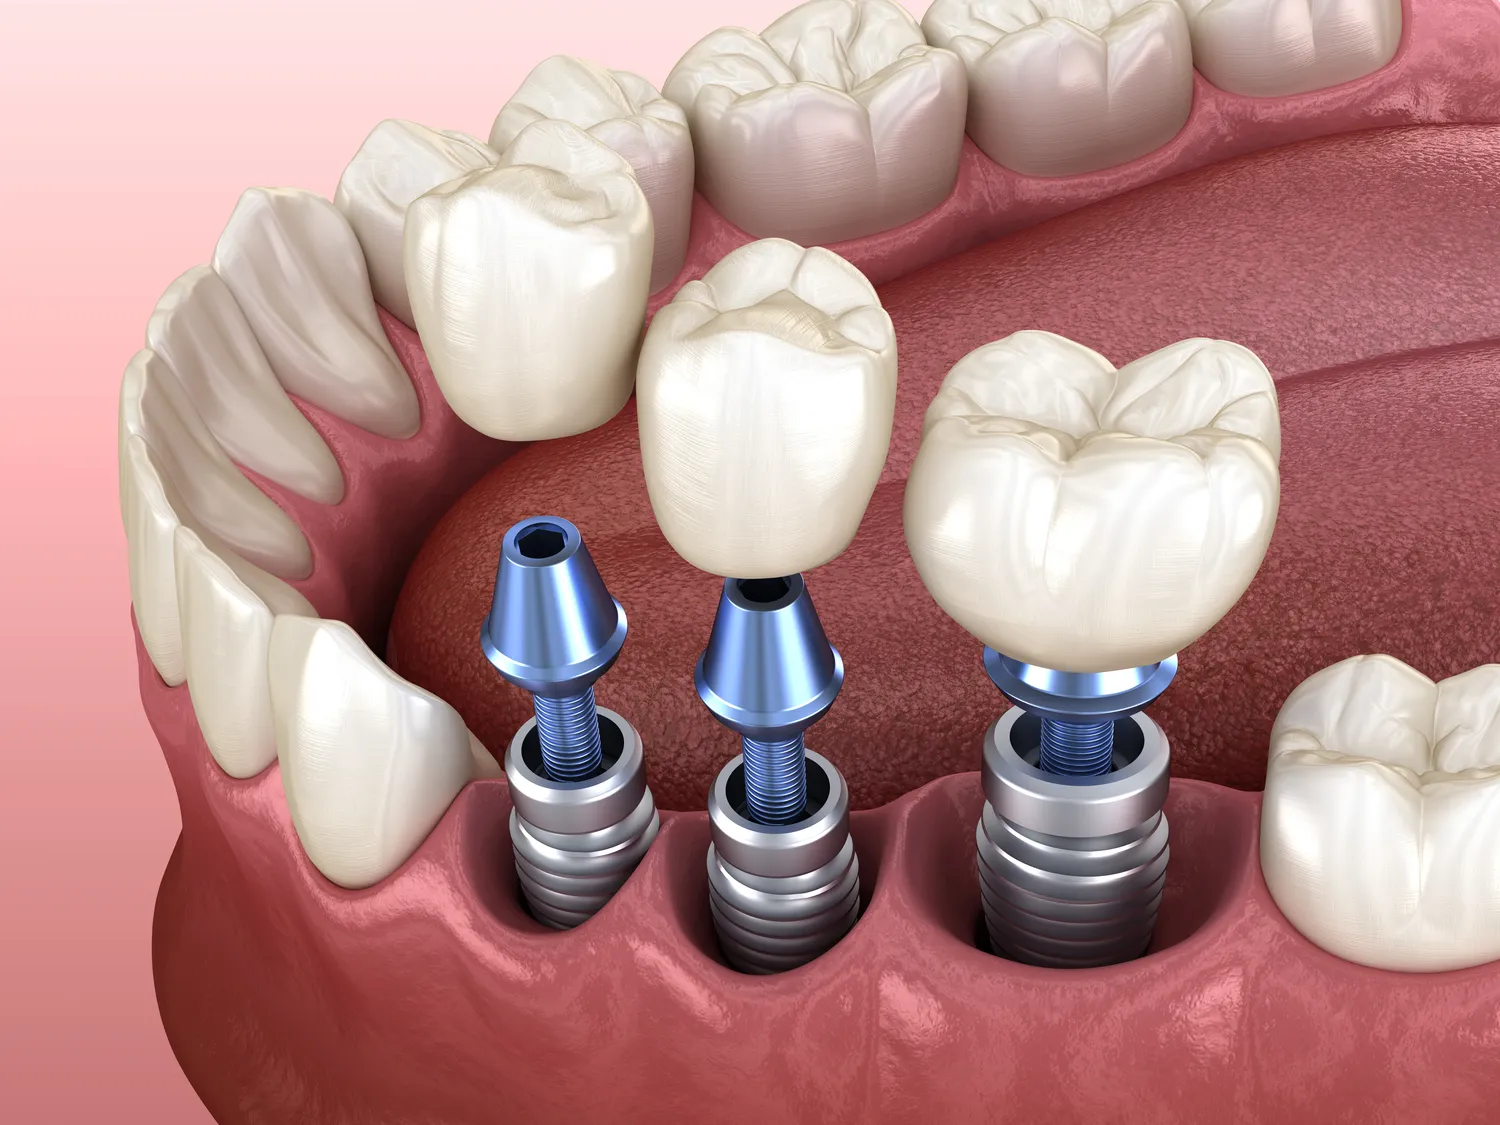

Zarobki stomatologów prowadzących własny gabinet w Polsce są bardzo zróżnicowane i zależą od wielu czynników. Przede wszystkim lokalizacja gabinetu ma kluczowe znaczenie, ponieważ w większych miastach, takich jak Warszawa czy Kraków, stomatolodzy mogą liczyć na wyższe dochody niż ich koledzy pracujący w mniejszych miejscowościach. Warto również zwrócić uwagę na specjalizację stomatologa, ponieważ niektóre dziedziny, takie jak ortodoncja czy implantologia, mogą przynosić znacznie wyższe przychody. Dodatkowo doświadczenie i renoma stomatologa mają ogromny wpływ na wysokość zarobków. Stomatolodzy z wieloletnim stażem oraz ci, którzy zdobyli uznanie w swojej dziedzinie, mogą ustalać wyższe ceny za swoje usługi. Właściciele gabinetów muszą także brać pod uwagę koszty prowadzenia działalności, takie jak wynajem lokalu, opłaty za media, zakup sprzętu oraz materiały dentystyczne.

Perspektywy rozwoju dla stomatologów w Polsce są obiecujące i pełne możliwości. Z roku na rok rośnie zapotrzebowanie na usługi stomatologiczne, a społeczeństwo staje się coraz bardziej świadome znaczenia zdrowia jamy ustnej. To sprawia, że wiele osób decyduje się na regularne wizyty u dentysty oraz korzystanie z nowoczesnych zabiegów estetycznych. Wzrost zainteresowania ortodoncją czy implantologią stwarza dodatkowe możliwości dla specjalistów w tych dziedzinach. Ponadto rozwijająca się technologia medyczna otwiera nowe horyzonty dla stomatologów pragnących poszerzać swoje umiejętności i oferować innowacyjne rozwiązania swoim pacjentom. Warto również zauważyć rosnącą popularność telemedycyny i konsultacji online, co może wpłynąć na sposób świadczenia usług stomatologicznych w przyszłości. Dla młodych dentystów istnieje wiele możliwości zatrudnienia w renomowanych klinikach czy szpitalach, a także możliwość otwarcia własnej praktyki po zdobyciu odpowiedniego doświadczenia.

Czy warto inwestować w nowoczesny sprzęt do gabinetu stomatologicznego?

Inwestowanie w nowoczesny sprzęt do gabinetu stomatologicznego jest kluczowym elementem zapewnienia wysokiej jakości usług oraz komfortu pacjentów. Nowoczesne technologie pozwalają na szybsze i bardziej precyzyjne diagnozowanie problemów zdrowotnych jamy ustnej oraz wykonywanie zabiegów o mniejszym stopniu inwazyjności. Dzięki temu pacjenci mogą liczyć na krótszy czas leczenia oraz mniejsze ryzyko powikłań po zabiegach. Dodatkowo nowoczesny sprzęt często wiąże się z większą efektywnością pracy dentysty, co przekłada się na możliwość obsługi większej liczby pacjentów w krótszym czasie. Warto jednak pamiętać o kosztach związanych z zakupem takiego sprzętu oraz jego serwisowaniem. Dlatego przed podjęciem decyzji o inwestycji warto dokładnie przeanalizować potrzeby swojego gabinetu oraz potencjalne korzyści płynące z posiadania nowoczesnych urządzeń.